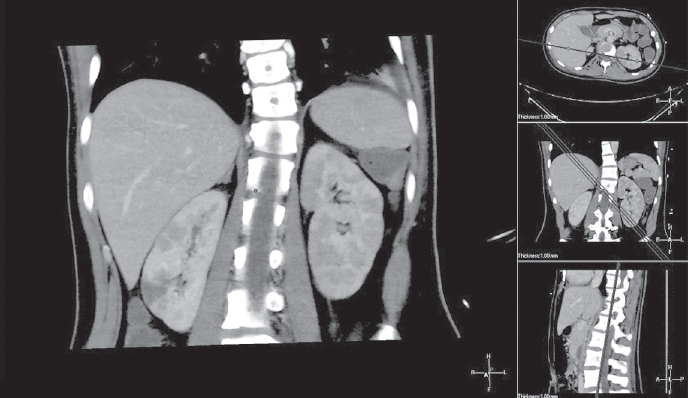

Оптимальные сроки операции на клапанах сердца у пациентов с активным инфекционным эндокардитом (ИЭ) до сих пор остаются спорными. Общеизвестно, что наиболее частой причиной смерти больных с левосторонним ИЭ является системная тромбоэмболия, поражающая церебральные, коронарные или почечные сосуды, которая может развиться еще до появления клинических проявлений поражения клапанного аппарата сердца. В настоящее время раннее хирургическое вмешательство рассматривается как наиболее эффективный метод лечения большинства форм активного ИЭ с поражением левых отделов сердца, которое подразумевает под собой выполнение хирургической коррекции еще до завершения полного терапевтического курса антибиотиков. Представляется клинический случай раннего успешного хирургического лечения инфекционного эндокардита митрального клапана (МК) у пациентки А., 16 лет. Заболевание протекало остро, с рецидивирующими эмболиями, повлекшими за собой инфаркт правой почки, а также остеомиелит левой ключицы. Хирургическое вмешательство производилось в срочном порядке из правосторонней переднебоковой торакотомии. Операция была проведена на 4-е сутки от момента госпитализации в кардиохирургический стационар. Однако потеря времени на догоспитальном этапе лечения, стремительное развитие грубых деструктивных изменений на МК, к сожалению, не позволили выполнить реконструктивное вмешательство. Произведено протезирование МК. Течение послеоперационного периода гладкое, на 3 сутки девочка была переведена в общесоматическое отделение. При контрольной эхокардиографии через 3 года сократительная функция миокарда сохранена, фракция выброса 65 %, функция протеза не нарушена.